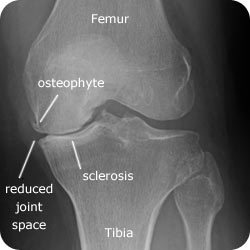

X - RAy:

Joint space narrowing

Osteophytes

Subchondral cysts

Subchondral sclerosis